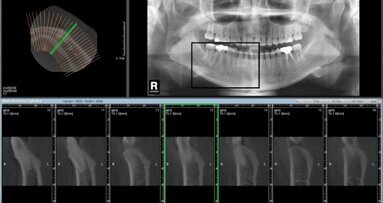

Σαράντα εξαχθέντες ανθρώπινοι γομφίοι κόπηκαν κατά μήκος του εγγύς-άπω άξονα. Η παρειακή και η γλωσσική αδαμαντίνη επιπεδώθηκε και έγινε μία τριγωνική παρασκευή βάθους 0,87 χιλ. και πλάτους 3 χιλ., που αναπαριστούσαν δύο λοξοτομήσεις 60°. Τα δοκίμια χωρίστηκαν τυχαία σε οκτώ ομάδες και αποκαταστάθηκαν με δύο διαφορετικές σύνθετες ρητίνες: μία νανορητίνη και μία μικροϋβριδική και τελειώθηκαν με δύο διαφορετικές τεχνικές στίλβωσης: δίσκους στίλβωσης ή ελαστικά στίλβωσης. Σε κάθε δοκίμιο, και τα δύο όρια στιλβώθηκαν με την ίδια τεχνική, το ένα όριο με κατεύθυνση από τη σύνθετη ρητίνη προς το δόντι και το άλλο με κατεύθυνση από το δόντι προς τη σύνθετη ρητίνη. Κατασκευάστηκαν αντίγραφα για εξέταση σε ηλεκτρονικό μικροσκόπιο σάρωσης (μεγέθυνση Χ200) και έγινε ποσοτική ανάλυση των ορίων με βάση τέσσερα κριτήρια. Τα δεδομένα αναλύθηκαν με ένα t-test δοκιμίων ανά ζεύγη, ένα t-test δύο δοκιμίων και μία μονόδρομη ανάλυση της διακύμανσης.

Τα αποτελέσματα έδειξαν ότι βρέθηκαν σημαντικές διαφορές στις περισσότερες ομάδες μεταξύ των κατευθύνσεων στίλβωσης, με την καλύτερη οριακή εφαρμογή να παρατηρείται με την κατεύθυνση από τη σύνθετη ρητίνη προς το δόντι. Οι διαφορές μεταξύ των τύπων την συνθέτων ρητινών και των τεχνικών στίλβωσης φαίνονταν να έχουν μία εξάρτηση από συγκεκριμένους συνδυασμούς σύνθετης ρητίνης, τεχνικής στίλβωσης και κατεύθυνσης στίλβωσης. Η εργασία κατέληξε στο συμπέρασμα ότι η στίλβωση με κατεύθυνση από τη σύνθετη ρητίνη προς το δόντι συντελεί σε καλύτερη οριακή εφαρμογή από ό,τι η στίλβωση με κατεύθυνση από το δόντι προς τη σύνθετη ρητίνη